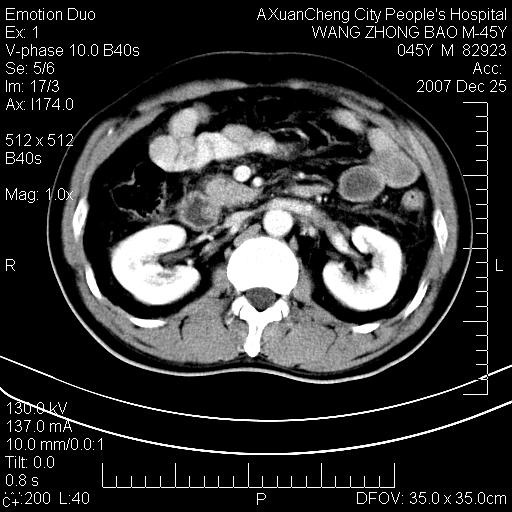

以下是引用qiuleiyu在2007-12-25 18:14:00的发言:[br]胰腺增大,周边渗出改变,肾前筋膜明显增厚,示少量积液.胆囊壁毛糙,周边少许渗出,胆总管壁厚,异常强化,然扩张不明显.结合病程急短;考虑;胆管炎,胆囊炎,胆源性胰腺炎可能大,请结合实验室检查及随访.

以下是引用lisihao在2007-12-25 14:23:00的发言:[br]急性水肿型胰腺炎[br]依据:1、胰腺弥漫性肿大,边缘稍毛糙;[br] 2、双侧肾周筋膜增厚,尤以左侧为甚(重要征象)[br] 3、双侧后胸膜增厚(刺激性炎症);[br] 4、结合病史,查血尿淀粉酶应该可以确诊。